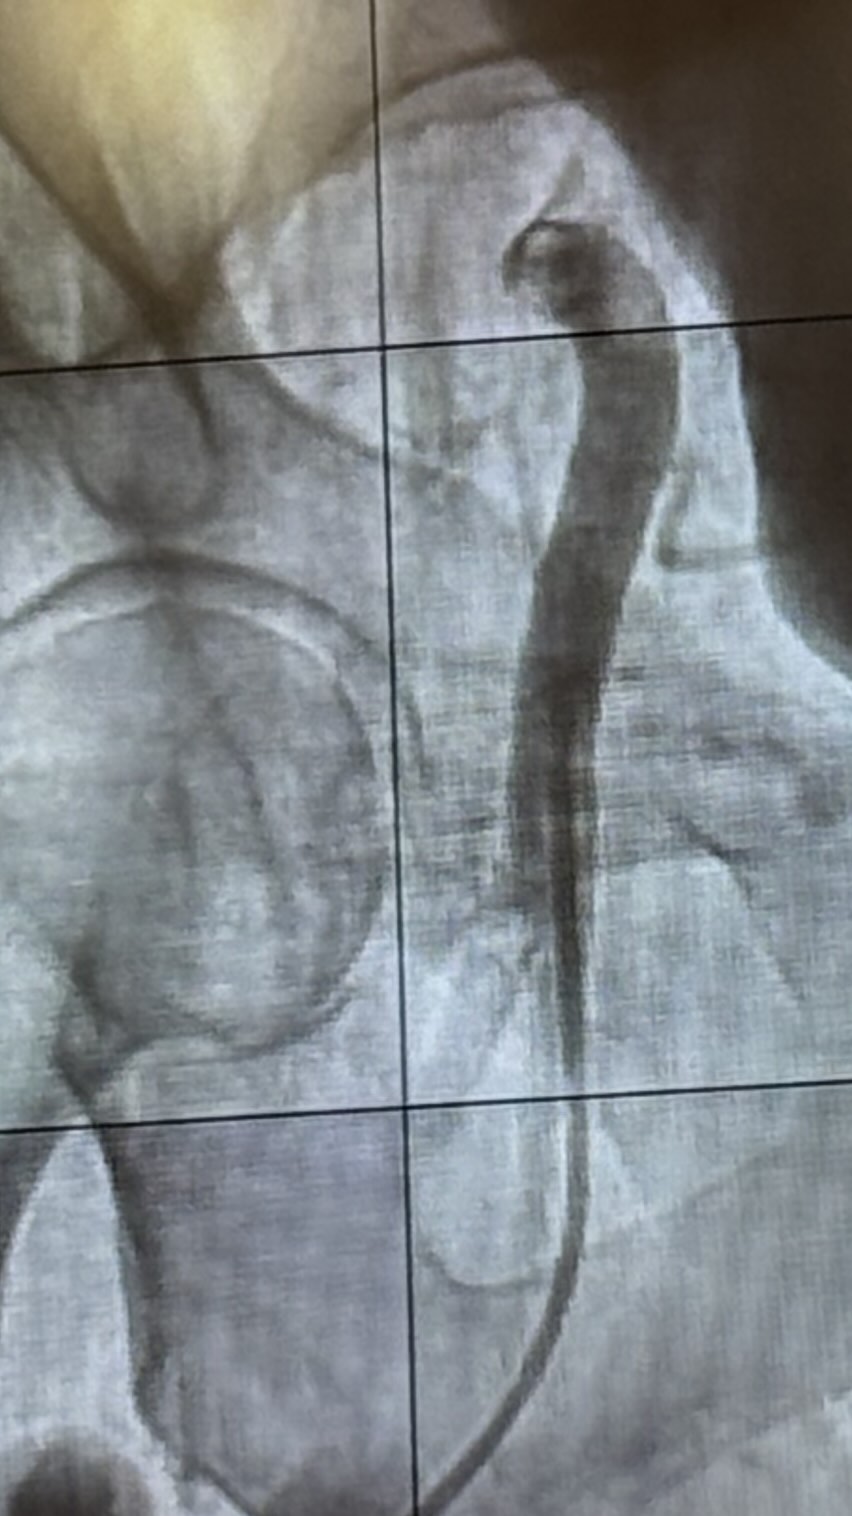

Renal artery denervation – Was done in 2007 through catheter. And did lower blood pressure. Kidney’s are greedy – they are very well innervated. Feedback loop to brain – they keep blood flow up. It becmoes overactive smpathetic system.

Nerves near the kidney are more important to ablate.

Radiofrequency mediated renal artery denervation – casuse a 10mm Hg drop in 24 hr ambulatory blood pressure primary endpoint.

Also ultrasound mediated rentar artery denervation.

All the equipment are put through a catheter.

Usually bilateral – specific energy to burn only the specific neurons.